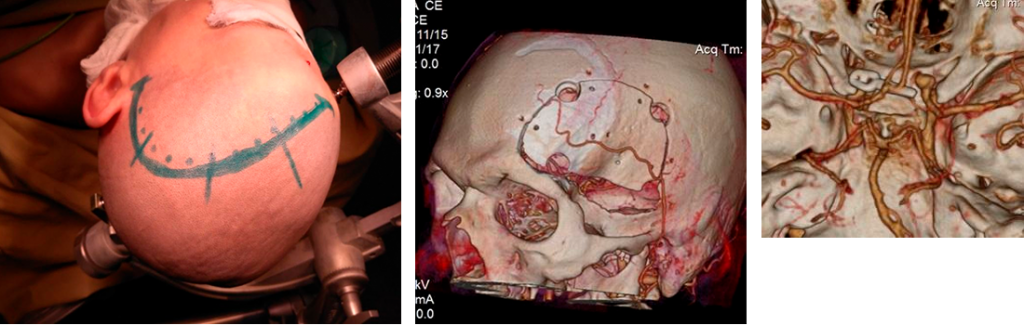

- Микрохирургическая операция с открытым доступом. Чтобы получить доступ к церебральным сосудам и аневризме, врач выполняет трепанацию черепа, и при помощи микрохирургических инструментов вскрывает оболочки мозга. Затем нейрохирург выключает аневризму из кровотока. Надёжным способом считается клипирование — наложение специальной клипсы на шейку (основание) мешотчатого выпячивания. Если нельзя выключить саму аневризму, то клипируется участок артерии ниже и выше патологического расширения.

- Эндоваскулярная малоинвазивная операция. Через кожный разрез хирург вводит в бедренную артерию катетер. Под контролем рентгеноскопии катетер направляется к месту расширения сосудистой стенки, где затем проводятся лечебные хирургические манипуляции.